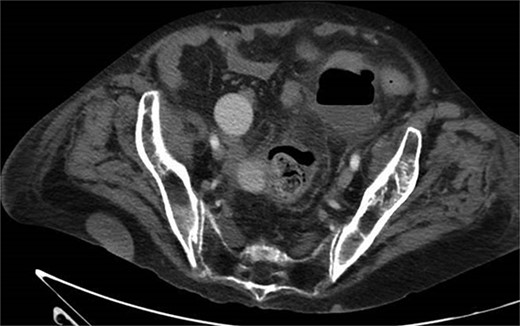

One month prior, the patient was admitted for complicated perforated sigmoid diverticulitis. Treatment included piperacillin-tazobactam (Zosyn), bowel rest, and fluid resuscitation. On hospital Day 6, her condition worsened with increased nausea, vomiting, and an elevated WBC count of 15. CT imaging revealed a 4.8 × 4.4 × 4.0 cm diverticular abscess, leading to CT-guided percutaneous drainage by interventional radiology (Figs 4–7). Cultures grew Citrobacter sedlakii and Enterococcus faecium vancomycin resistant Enteroccus (VRE), and treatment was adjusted to include Bactrim, followed by daptomycin and levofloxacin. The abscess resolved after 3 weeks, and the drain was removed before discharge. The patient was instructed to follow up with her surgeon and undergo a 6-week interval colonoscopy.

CT showing resolution of abscess with IR pigtail drain in place.